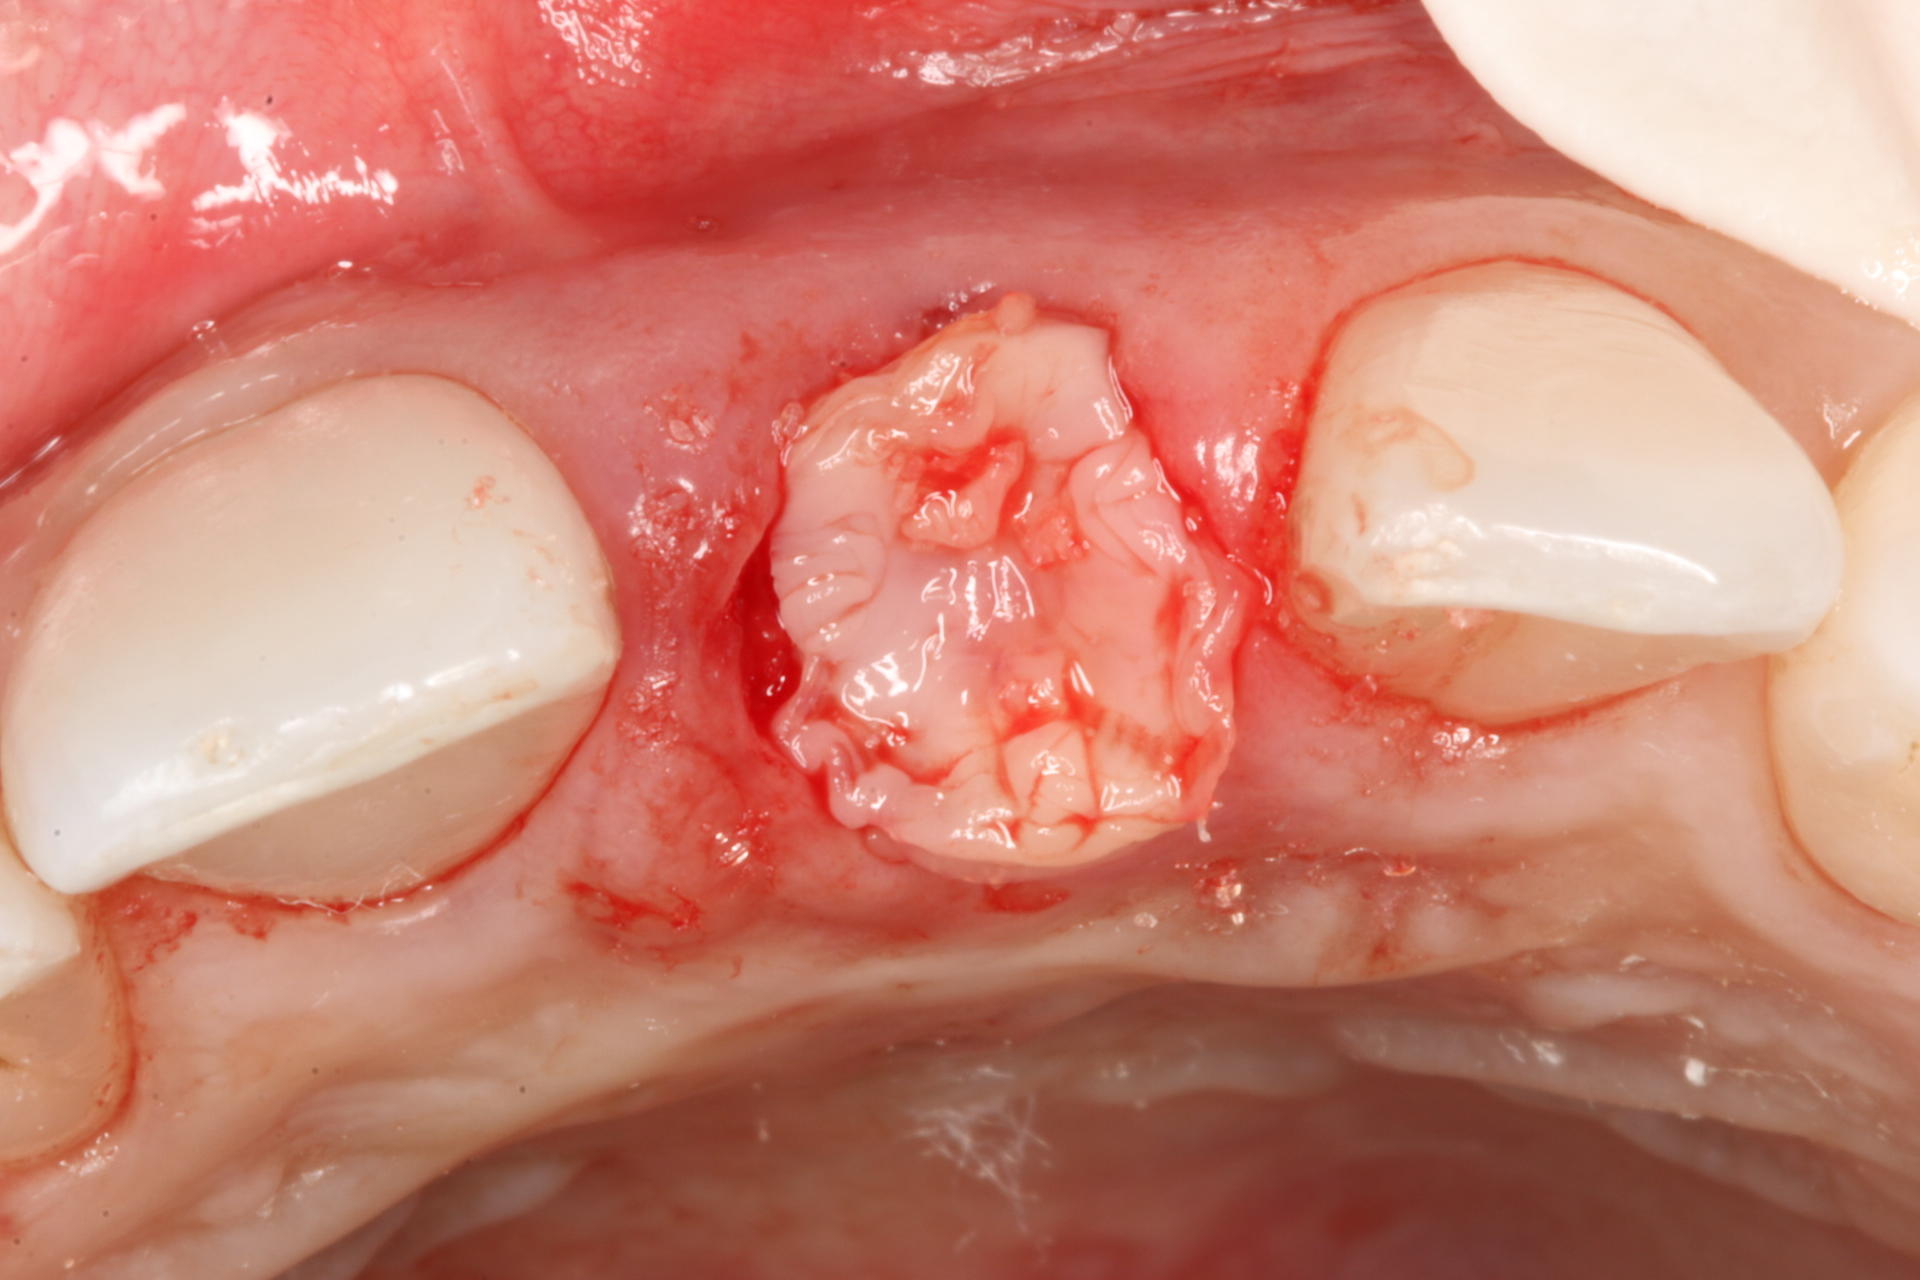

Dedicated to understanding and implementing the ridge augmentation blue print. All about socket grafting, bone, soft tissue, membranes, PRF, materials. We also included a hands-on exercise for soft tissue grafting and suturing.

• Tunnel creation for grafting and emergence profile enhancement

• The pedicle palatal graft - powerful vascular grafting